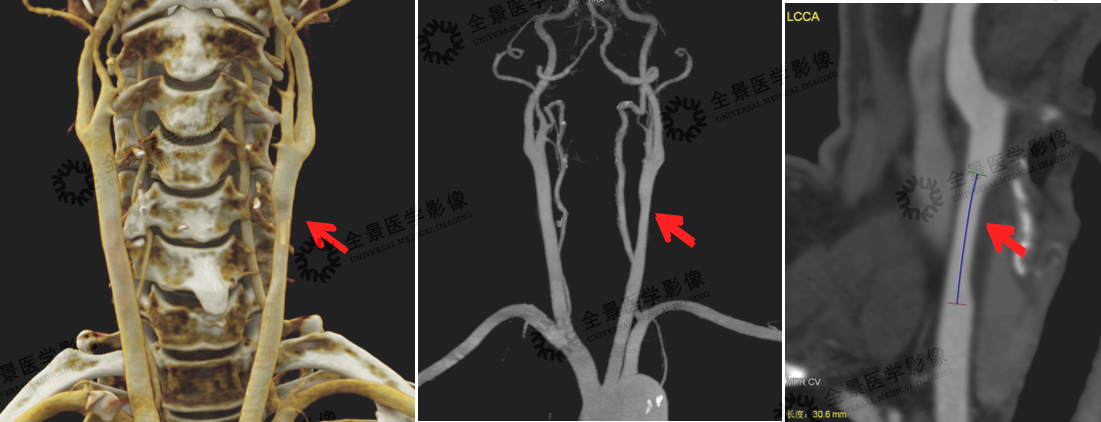

头颈部VR容积重建,可显示头颈部整体血管情况。MIP、MPR、CPR等重建方式可清晰显示病变细节,如血管斑块的性质及稳定性、血管腔狭窄的位置、狭窄程度、有无血管变异、血栓或侧枝循环形成等情况;同时也可作为血管支架置入术后随访常用方式。

案例:左侧颈总动脉近分叉处见长节段斑块形成,病变长度约30.6mm,性质为软斑块(含脂质成分多,危险程度较高),管腔直径最重处接近中度狭窄(约50%)。